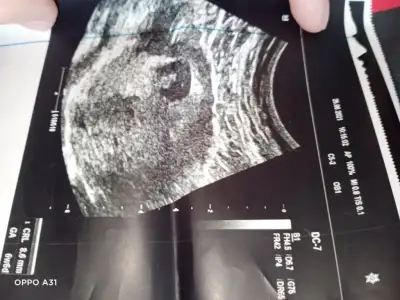

Kız gibi sanki emin olamadımEki Görüntüle 2892053 Eki Görüntüle 2892054 @Ikra meyra acaba müsait olunca bakar mısın? 11+6 oldu belli olur mu biraz?

Teşekkür ederimKız gibi sanki emin olamadım